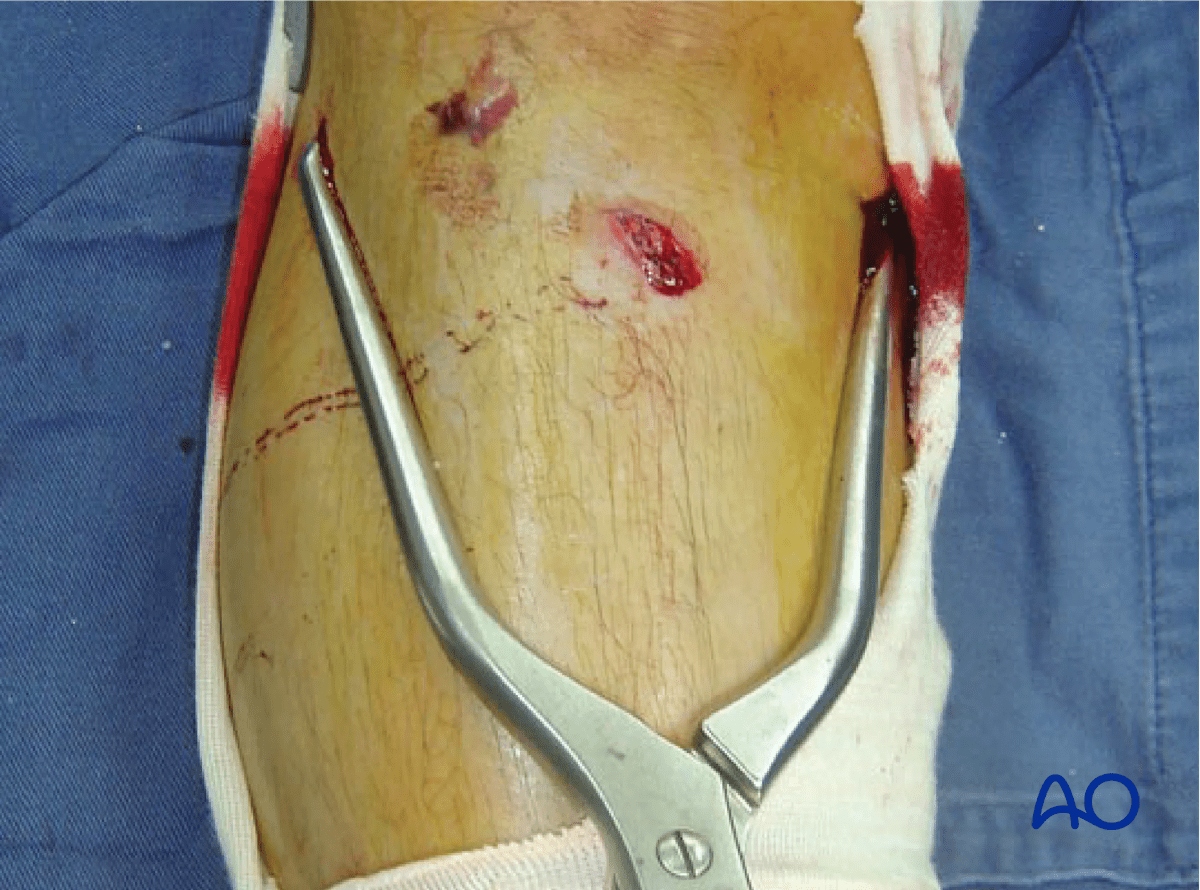

Indirect reduction may be attempted by external manipulation of the fractured fragment using clamps. The accuracy of the reduction should be checked with radiographic confirmation with or without arthroscopy. In cases where adequate closed reduction is not achieved the joint must be opened in order to carry out an anatomical reduction of the joint surface. This may also be necessary to repair the lateral meniscus which may be injured in association with these fractures.

Proximal tibia lateral plateau split fracture – reduction with clamps

Clinical image showing the clamp application.

Proximal tibia fracture – clinical image showing clamp application